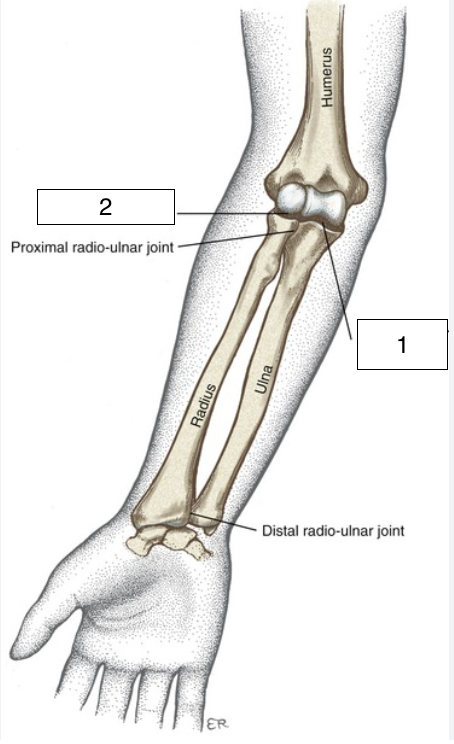

what is the highlighted joint (number 1)?

humeroulnar

what is the highlighted joint (number 2)?

humeroradial

what kind of joint is the humeroulnar joint?

synovial, hinge joint

what kind of joint is the humeroradial joint?

synovial, modified ball-and-socket and hinge joint